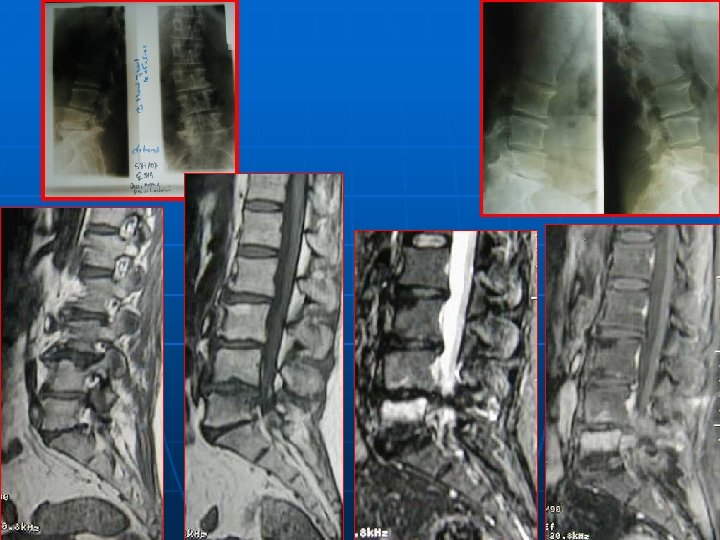

IRM n n EXAMEN CLE INCONVENIENTS : * statique * scoliose plan de coupe différent pour les étages STENOSE : centrale, foraminale ou associée (intérêt des coupes latérales foraminales) STRATEGIE OPERATOIRE+++ : ° état des disques (Modic? ) ° direction interligne articulaire : déstabilisation postopératoire?

BILAN RADIOLOGIQUE STANDARD +++ n n n Disque intervertébral: * pincement * conservation hauteur discale voir (disque défaillant) Signes d’arthrose intersomatique Ostéoporose

BILAN RADIOLOGIQUE STANDARD +++ n n SIGNES INDIRECTS DE CLE: *sagittalisation de l’IA *hypertrophie des articulaires *pédicules courts Spondylolesthésis dégénératif sagittal et frontal Visée pédiculaire: taille du pédicule+point d’entée CLICHES DYNAMIQUES INDISPENSABLES : Instabilité surtout en flexion